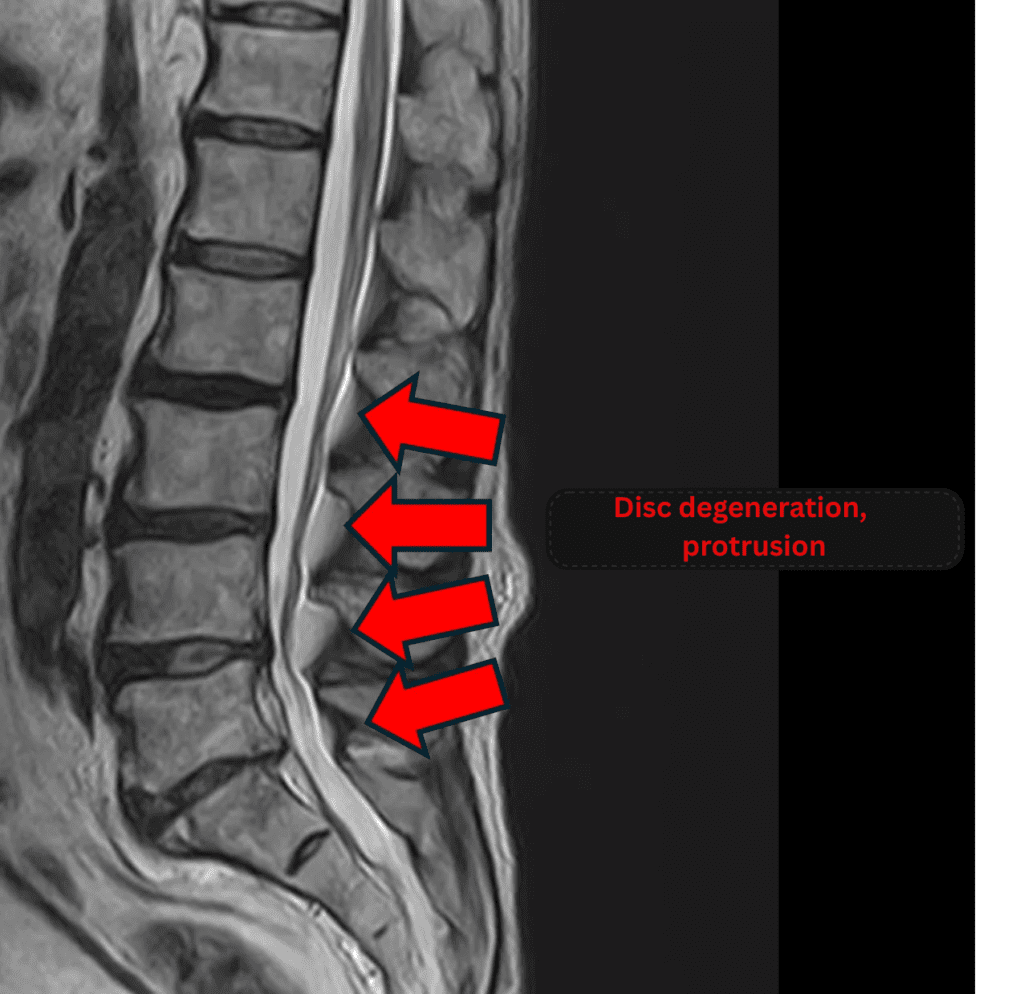

Imaging and findings

- L2/3, L3/4: Disc degeneration and bulging

- L4/5: Disc degeneration, bulging, and endplate degeneration

- L5/S: Disc degeneration, bulging, and annular tear

The above findings were also observed on the imaging.

Compression of the spinal canal caused by disc degeneration and bulging at L2/3, L3/4, L4/5, and L5/S was considered the most likely cause of the patient’s symptoms.